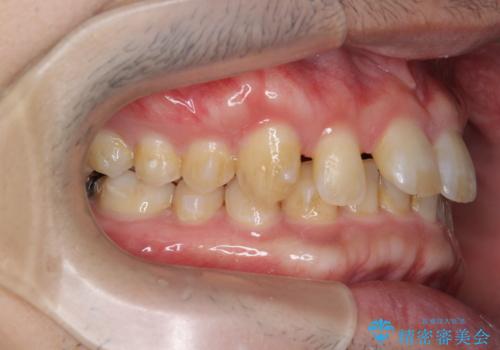

ディープバイトのマウスピース矯正

- 飛び出してしまい、隙間のある前歯をきれいに並べたい、と矯正治療を希望され来院されました。

上顎前歯を後方に引き、隙間を閉じるためには下顎前歯の絶対的な圧下を行い、深い噛み合わせを改善することが必要です。

圧下は歯の動きの中でも難しい動きの一つで時間がかかることが多いです。

前歯でチューイーをしっかり噛み、咬合圧を伝えたことで下顎前歯が圧下し、上顎前歯の隙間を閉じることができました。